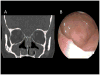

Figures